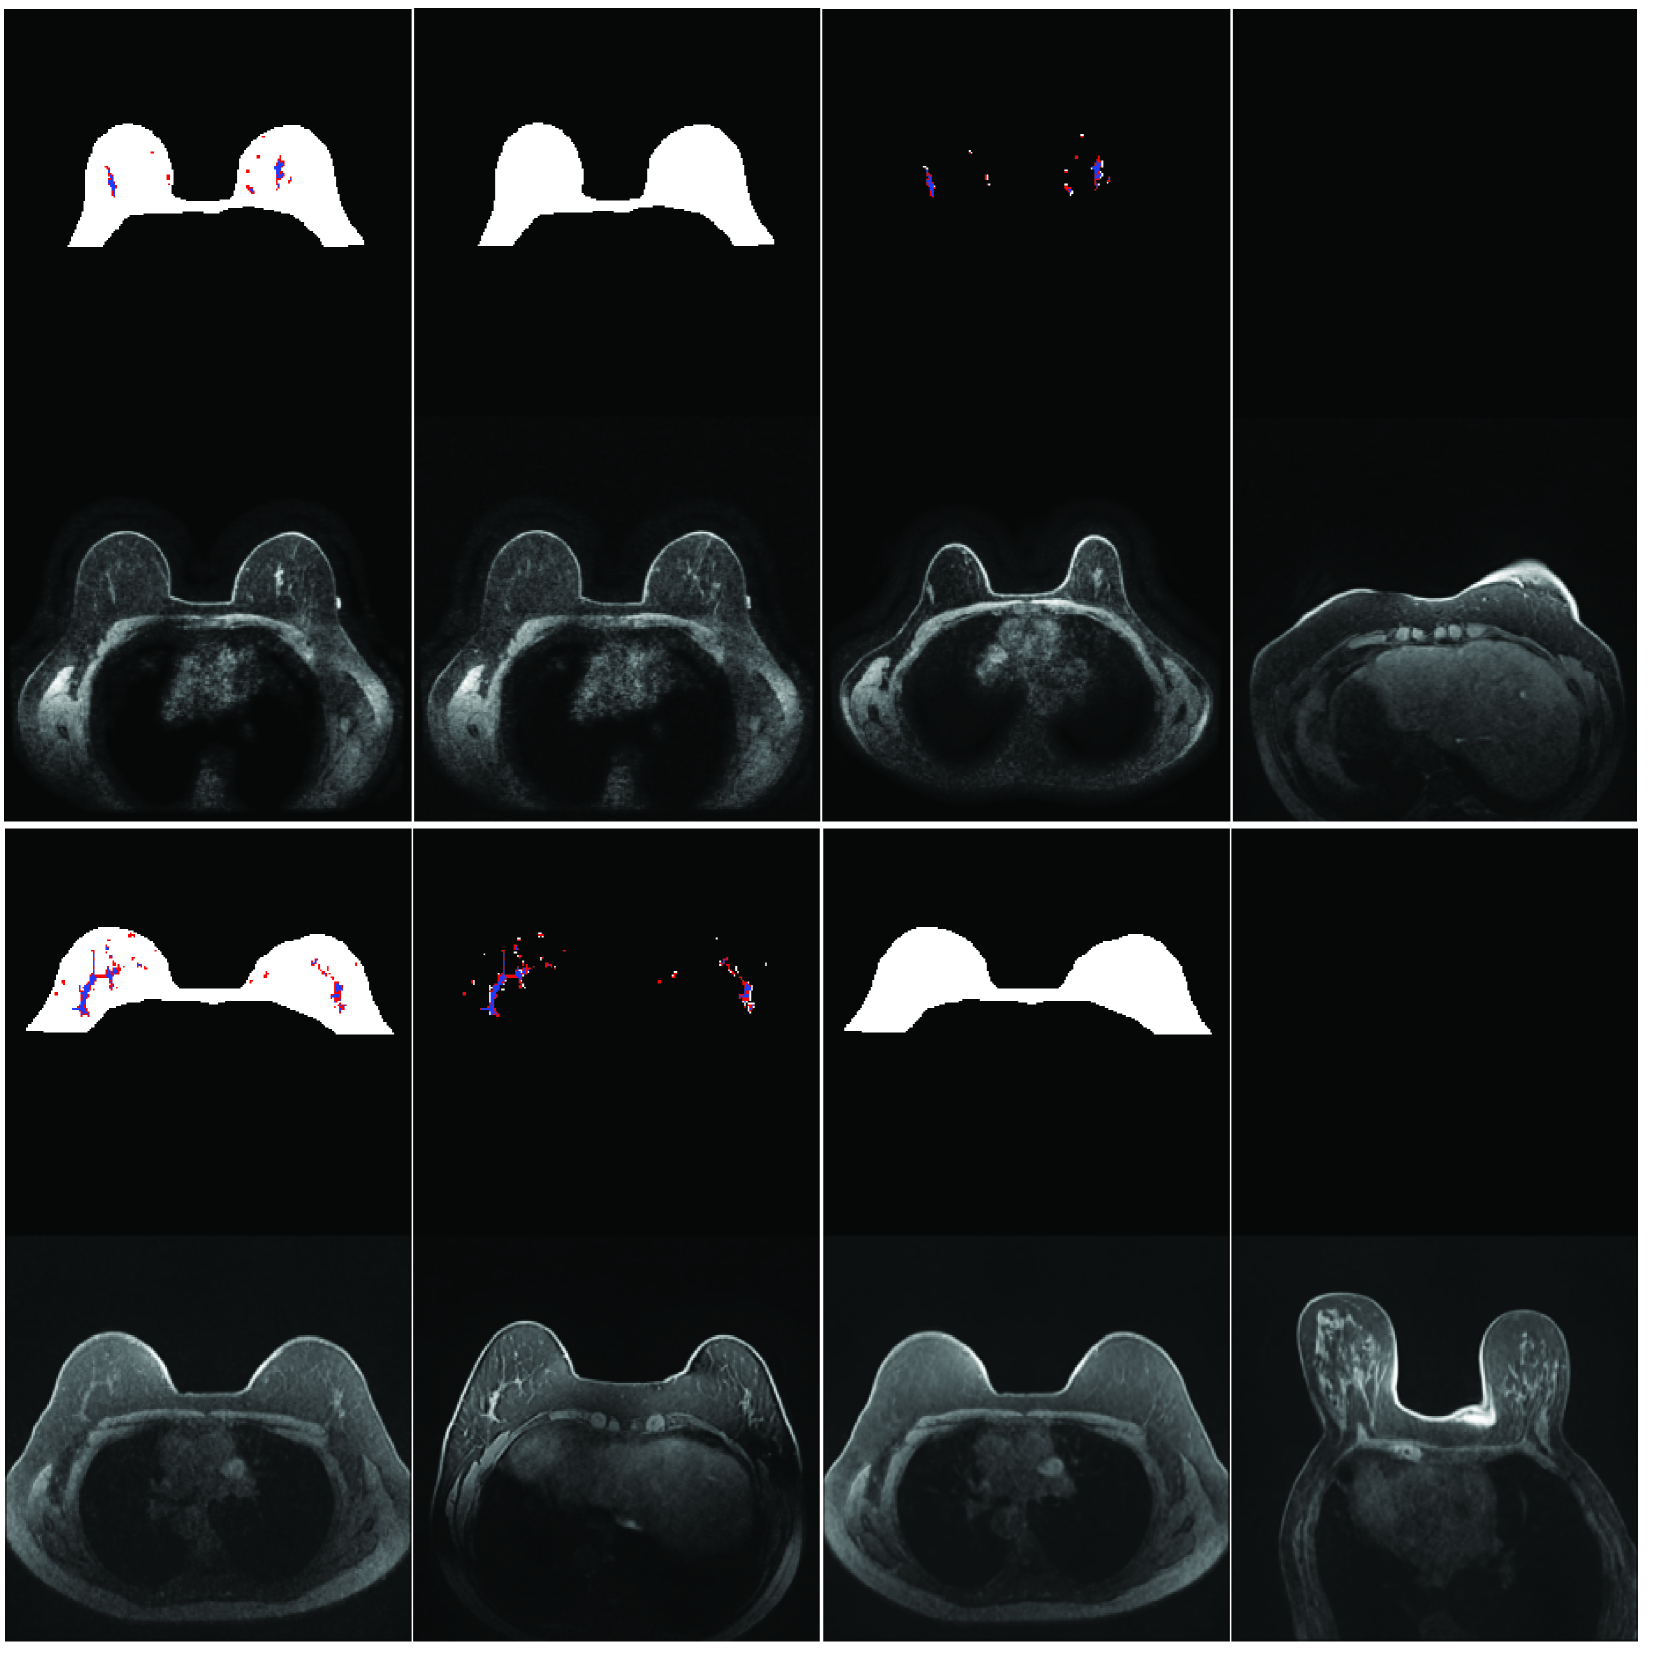

fig:samples_ablated

We will next explore our model’s ability to be conditioned on a range of combinations of present or missing anatomical classes in input masks, following our mask-ablated training algorithm (Sec. 1.3). In Fig. LABEL:fig:samples_ablated we demonstrate the effect on generated images of ablating certain classes from an input mask for breast MRI (more examples, including for CT Organ, in Appendix D). For example, we see that constraining the blood vessels and fibroglandular tissue (BV+FGT) in breast MRI, yet keeping the breast free, results in images that have the latter two classes pre-registered while the breast shape varies, and vice-versa.

Notably, we also see that when the model is provided with an empty mask (unconditioned), it typically generates more anatomically realistic images than the unconditionally-trained model does (e.g., compare the bottom right image in Fig. LABEL:fig:samples_ablated to the rightmost image in Fig. LABEL:fig:eg_imgs), due to the mask-ablated training acting as self-supervised learning of more realistic object representations (somewhat analogous to MAE [He et al.(2022)He, Chen, Xie, Li, Dollár, and Girshick]; see Appendix B). This is important because the model has both the anatomical realism of a model trained with full mask guidance and the ability to generate new diverse samples without needing input masks.

We show additional samples for both datasets for all models in Fig. LABEL:fig:samples_many (to supplement Fig. LABEL:fig:samples). Similarly, we show more samples with various classes removed from input masks to illustrate the effect of mask-ablated training (Sec. 1.3) in Figures LABEL:fig:samples_many_abla_breast and LABEL:fig:samples_many_abla_ct for breast MRI and CT organ, respectively, to supplement Fig. LABEL:fig:samples_ablated.

fig:samples_many_abla_breast